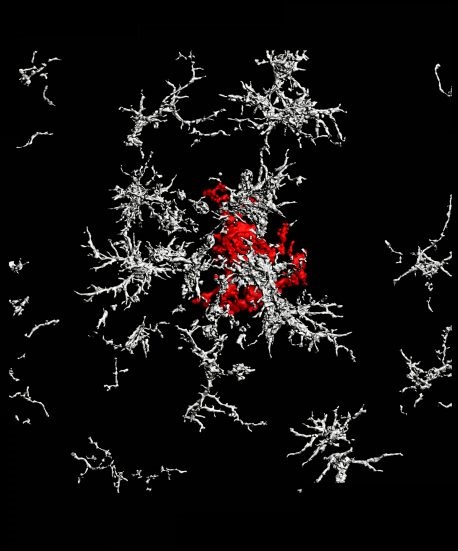

传统观点认为,大脑中被称为小胶质细胞的清除垃圾的免疫细胞通过“吃掉”斑块来抑制斑块的生长。Salk的科学家们发现,小胶质细胞反而促进了致密核心斑块的形成,而这种作用会将细小的斑块物质从神经元中清除,从而导致细胞死亡。这项研究发表在2021年4月15日的《Nature Immunology》杂志上,表明致密的核心斑块起着保护作用,因此,破坏它们的治疗可能弊大于利。

斑块的形式多种多样,但最常见的两种是“弥漫性”和“致密核心”。弥漫性斑块组织松散,无定形云。致密的核心斑块有一个紧密的中心,周围有一个光环。科学家们普遍认为,这两种类型的斑块都是由淀粉样前体蛋白(App)前体分子的过量产生自发形成的。但是,根据新的研究,实际上是小胶质细胞通过弥漫性淀粉样β原纤维形成致密的核心斑块,作为细胞清理的一部分。

他们深入挖掘,用活体成像追踪致密的核心斑块。令他们大吃一惊的是,研究小组发现,在小胶质细胞吞噬弥漫性斑块后,它将吞噬的β淀粉样蛋白转移到一个高酸性的隔间,并将其转化为高度致密的聚集体,然后转移到致密的核心斑块中。研究人员认为这是一种有益的机制,组织扩散成致密的核心斑块,并清除细胞间的碎片环境。

“我们的研究似乎表明,当致密核心斑块较少时,”这篇论文的第一作者You Tonghuang说。“似乎还有更多的不利影响。随着斑块的扩散,有大量营养不良的神经突起,这是神经元损伤的代名词。我不认为临床上有明确的决定哪种形式的斑块或多或少是有害的,但通过我们的研究,我们似乎发现致密的核心斑块更为良性。”